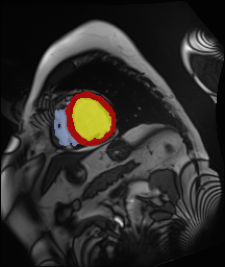

Medical data often exhibits long-tail distributions with heavy class imbalance, which naturally leads to difficulty in classifying the minority classes (i.e., boundary regions or rare objects). Recent work has significantly improved semi-supervised medical image segmentation in long-tailed scenarios by equipping them with unsupervised contrastive criteria. However, it remains unclear how well they will perform in the labeled portion of data where class distribution is also highly imbalanced. In this work, we present ACTION++, an improved contrastive learning framework with adaptive anatomical contrast for semi-supervised medical segmentation. Specifically, we propose an adaptive supervised contrastive loss, where we first compute the optimal locations of class centers uniformly distributed on the embedding space (i.e., off-line), and then perform online contrastive matching training by encouraging different class features to adaptively match these distinct and uniformly distributed class centers. Moreover, we argue that blindly adopting a constant temperature $\tau$ in the contrastive loss on long-tailed medical data is not optimal, and propose to use a dynamic $\tau$ via a simple cosine schedule to yield better separation between majority and minority classes. Empirically, we evaluate ACTION++ on ACDC and LA benchmarks and show that it achieves state-of-the-art across two semi-supervised settings. Theoretically, we analyze the performance of adaptive anatomical contrast and confirm its superiority in label efficiency.